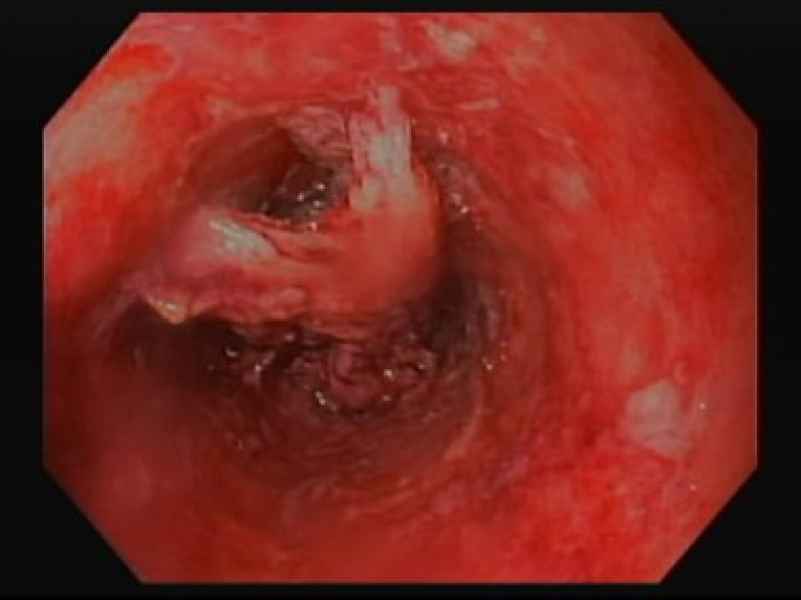

From ring to ring on the road to the eosinophilic abyss - a doubly complicated presentation of Eosinophilic oesophagitis!

Fotografia